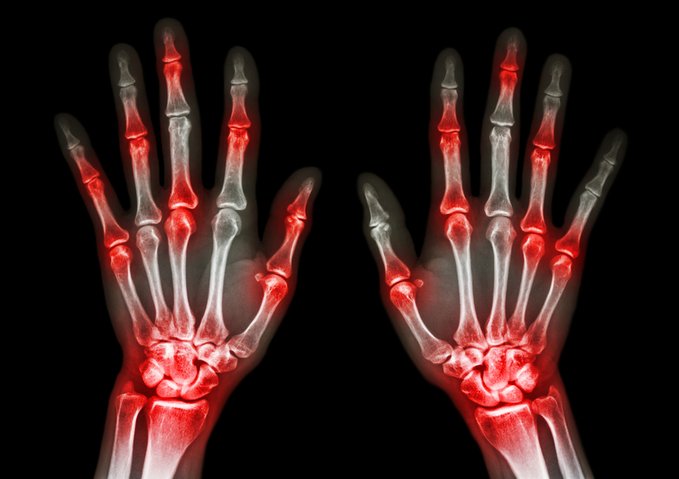

Esta revisión describe las herramientas de evaluación y las medidas de resultado utilizadas en la evaluación de los pacientes con artritis psoriásica. Resume el enfoque de la terapia, incluidas las intervenciones no medicinales como la educación, los cambios en el estilo de vida, la fisioterapia y la terapia ocupacional. Se discute la evidencia sobre los tratamientos farmacológicos, incluidos los fármacos utilizados para el alivio sintomático, como los antiinflamatorios no esteroideos, y los utilizados para controlar el proceso de la enfermedad. BMJ 21 de noviembre de 2024